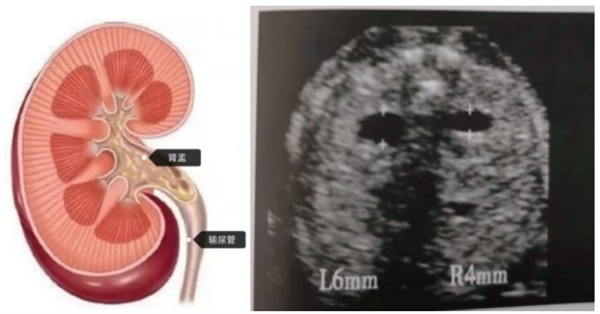

信号二:肾盂分离——宝宝憋的一泡“尿”

B超单提示:“肾盂分离”或“肾盂轻度扩张”

它是什么?简单说,就是肾脏和输尿管连接的“小水池”里尿液暂时较多,被撑宽了。

(肾盂分离<4mm(孕中期)和<7mm(孕晚期)属于安全范围)

医生解密:

1.多是生理现象:宝宝在子宫里会憋尿,B超时刚好膀胱满,就会看到“分离”。

2.数值是关键:只要分离径线在安全值内,就无需担心。

3.男宝更常见。

4.需要复查?即便稍超安全值,也只需定期B超监测。大部分宝宝出生后都能自行缓解。